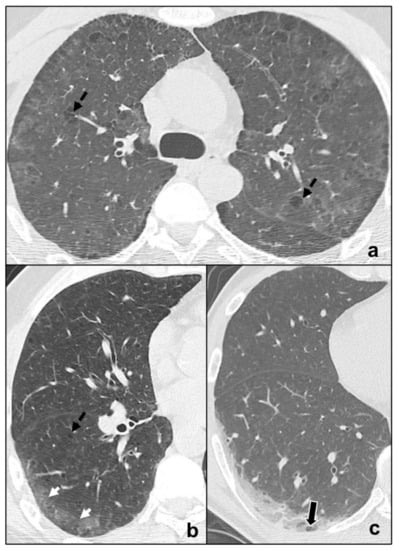

- Early phase/Stage 1 refers to days 0–4, and ground glass opacities represent the main radiological findings (Figure 1a);

- Progressive phase/Stage 2 refers to days 5–8, and the hallmark is represented by crazy paving pattern (Figure 1b) coexisting with extensive ground glass opacities and initial consolidative foci;

- Peak phase/Stage 3 is typical of days 9 to 13, and CT shows consolidations (Figure 1c), sometimes surrounded by a ground glass halo (halo sign);